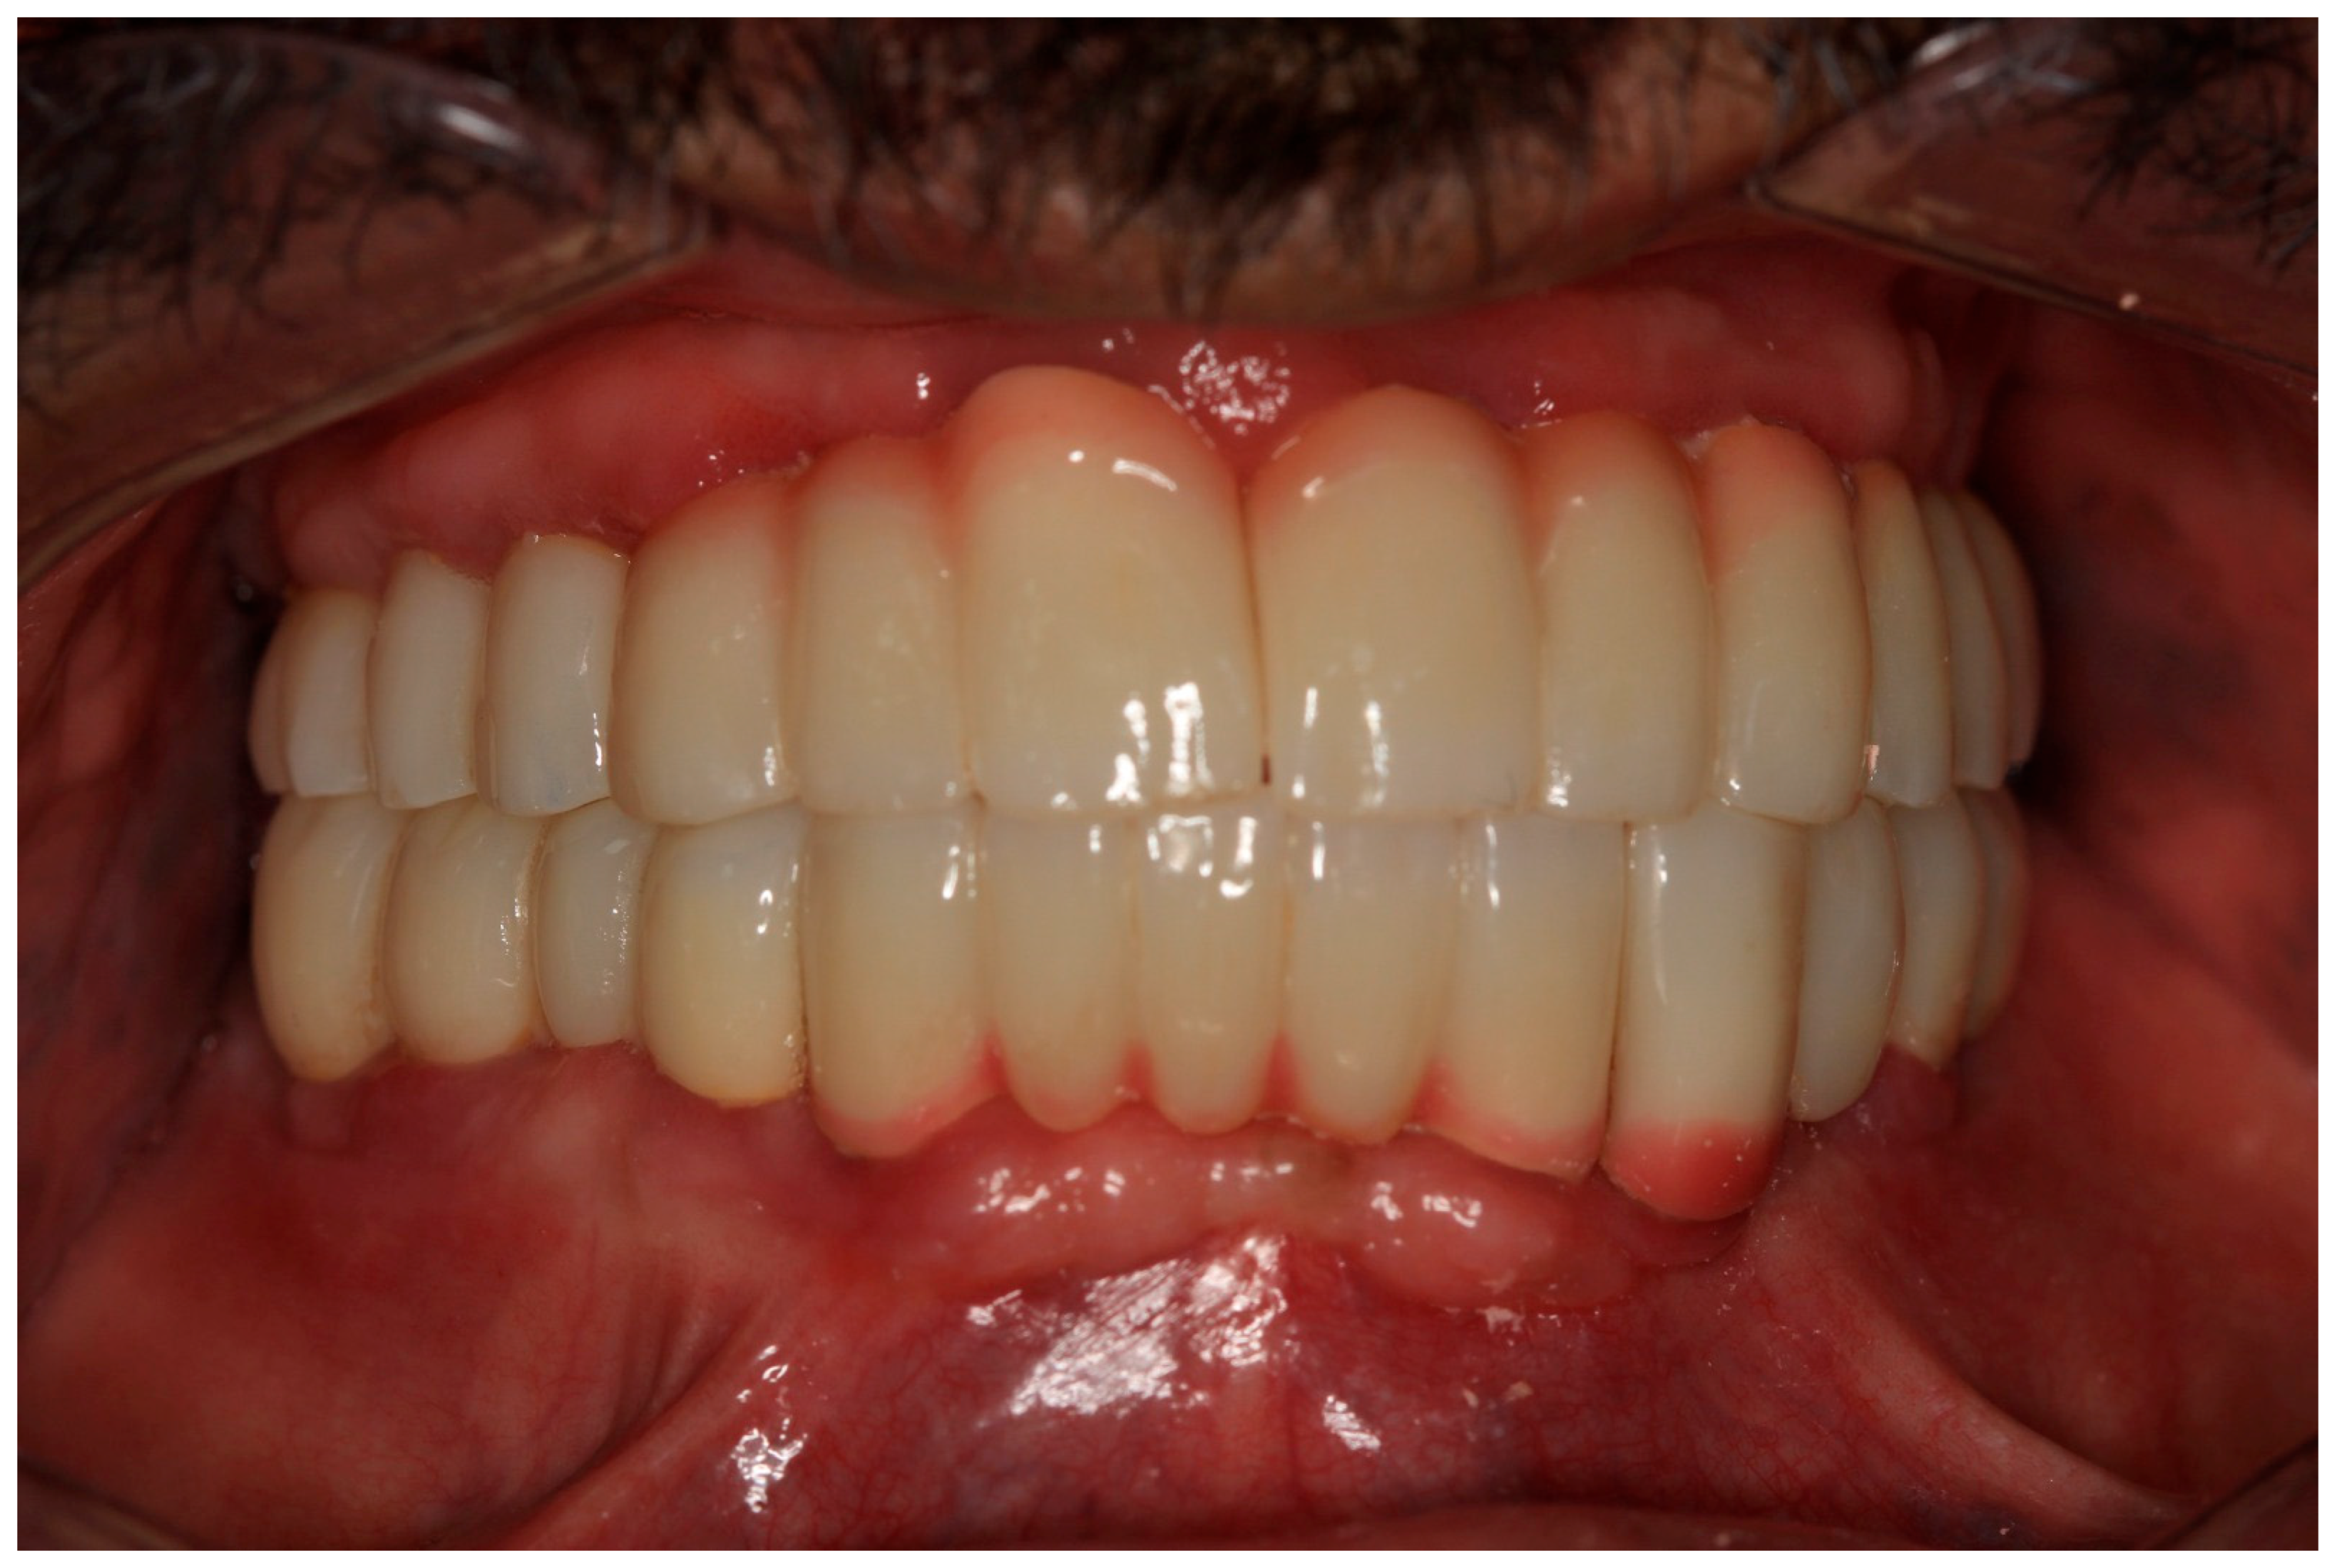

2.6. Sixth Visit

During the three-year follow-up period from October 2022 through September 2025, the patient was regularly recalled for evaluation. The peri-implant soft tissues remained healthy throughout the observation period. The gingiva surrounding the implants was consistently pink, firm, and showed no bleeding or suppuration upon probing of the peri-implant sulcus. At the last visit, probing depths ranged from 2–4 mm (mean 3 mm) in the maxillary arch and 1–3 mm (mean 2 mm) in the mandibular arch. No clinical signs of inflammation, edema, or granulation tissue were observed, indicating stable peri-implant mucosa and sustained biocompatibility of the materials used. Radiographic assessment revealed no crestal bone loss, and the prosthetic components remained functionally and esthetically intact, with no evidence of wear, fracture, or loosening. The patient reported high satisfaction regarding comfort, function, and appearance, further supporting the clinical success and reliability of this treatment approach (Figure 16 and Figure 17).

Figure 14. The final prostheses.

Figure 16. Follow-up photo.